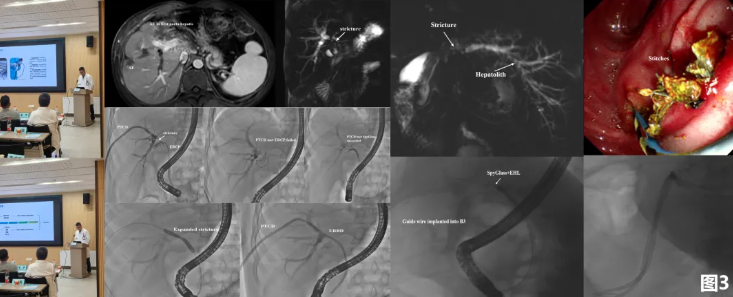

沙龙上,多位专家分享了前沿经验与创新方案:李宇副主任医师作了题为《肝胆术后胆道并发症的治疗》的报告,系统阐述了其团队多年积累的胆管狭窄综合治疗经验,涵盖内镜、介入、磁外科及再次手术的决策与技巧,即外科手术-ERCP-US/EUS(超声/超声内镜检查)-PTCS(经皮经肝胆道镜检查)-磁压榨技术的全能型人才。

郑海波副主任医师分享了《胆道子镜在肝泡型棘球蚴病术后胆道并发症中的应用》,展示了科室利用ERCP和先进胆道子镜技术,精准诊治肝包虫病这一高原特色疾病术后胆道并发症的宝贵经验。

尤为引人注目的是,科室万陈飞主治医师汇报的《磁力疏通技术治疗胆囊切除术后完全性胆道梗阻》,为胆道损伤提供了一条全新的微创治疗思路。该技术利用磁力实现原位微创再通,使患者避免再次或多次手术,体现了科室在处理棘手并发症时拥有的多元化、微创化先进手段。会议间歇,与会人员展开热烈讨论,科室团队逐一解答。

学术交流的热度未减,捷报又从国际赛场传来。3月29日,在四川大学华西医院主办的“2026一带一路肝脏微创技术国际培训班项目启动仪式暨《中国普外基础与临床杂志》腔镜手术视频比赛”中,主治医师万陈飞代表医院参赛,其报送的手术视频《胆道闭锁磁压榨再通术》,在来自 11 个国家的众多国内外优秀参赛作品中脱颖而出,荣获大赛三等奖。该奖项不仅是对普通外科微创技术的肯定,更是对西安交通大学第一附属医院全球领先的磁外科技术体系的又一次国际认可。